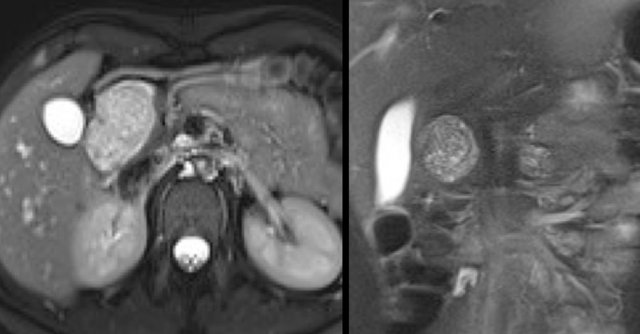

CT-image of a 51 year old woman with a history of gallstones and abdominal pain.

There is a hypodense lesion with central calcification in the head of the pancreas.

The lesion has a lobulated contour.

Continue with the MR.

MRI better demonstrates the morphologic features of the lesion (fig).

On T2WI the lesion is multicystic.

Note the central low signal due to the central scar with calcifications.

Although some of the cysts are rather large, this is still a characteristic appearance of a serous cystic adenoma (macrocystic form).

Another example of a serous cystic neoplasm (Fig).

The contrast-enhanced image on the right shows a hypodense lesion with central calcification in the body of the pancreas and subtle enhancement of septations

Notice that on CT it is very difficult to appreciate the cystic nature of these lesions and you might think that you are dealing with a pancreatic adenocarcinoma.

MRI will easily demonstrate the cystic nature of these lesions (fig).

The T2WI with fatsat nicely demonstrates a lobulated hyperintense lesion with central scar, which is characteristic of a SCN.